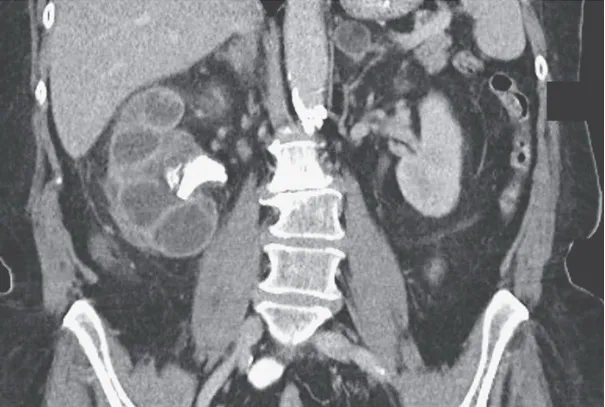

Uma causa incomum de hematúria glomerular intermitente!

Uma causa incomum de hematúria glomerular intermitente!

Hematúria pós infecção, caso clínicos para auxiliar no entendimento de causas glomerulares comuns e raras...